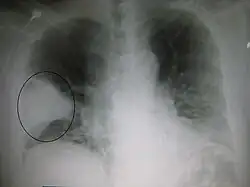

Abnormalities

Nodule

A lung nodule is a discrete opacity in the lung which may be caused by:

Cavities

A cavity is a walled hollow structure within the lungs. Diagnosis is aided by noting: